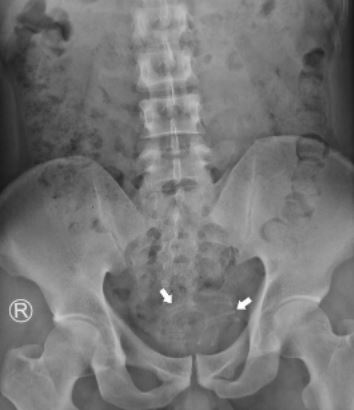

The strange insertion was carried out “based on s3xual pleasure and gratification,” and the wire that had lodged itself in his bladder was “visible and quickly identified” by the hospital team.

The wire had been coiled and fortunately not attached to the bladder wall, with an extraction carried out using grasping forceps, while the earphone wire was said to be 2-3mm in size and 80cm in length.